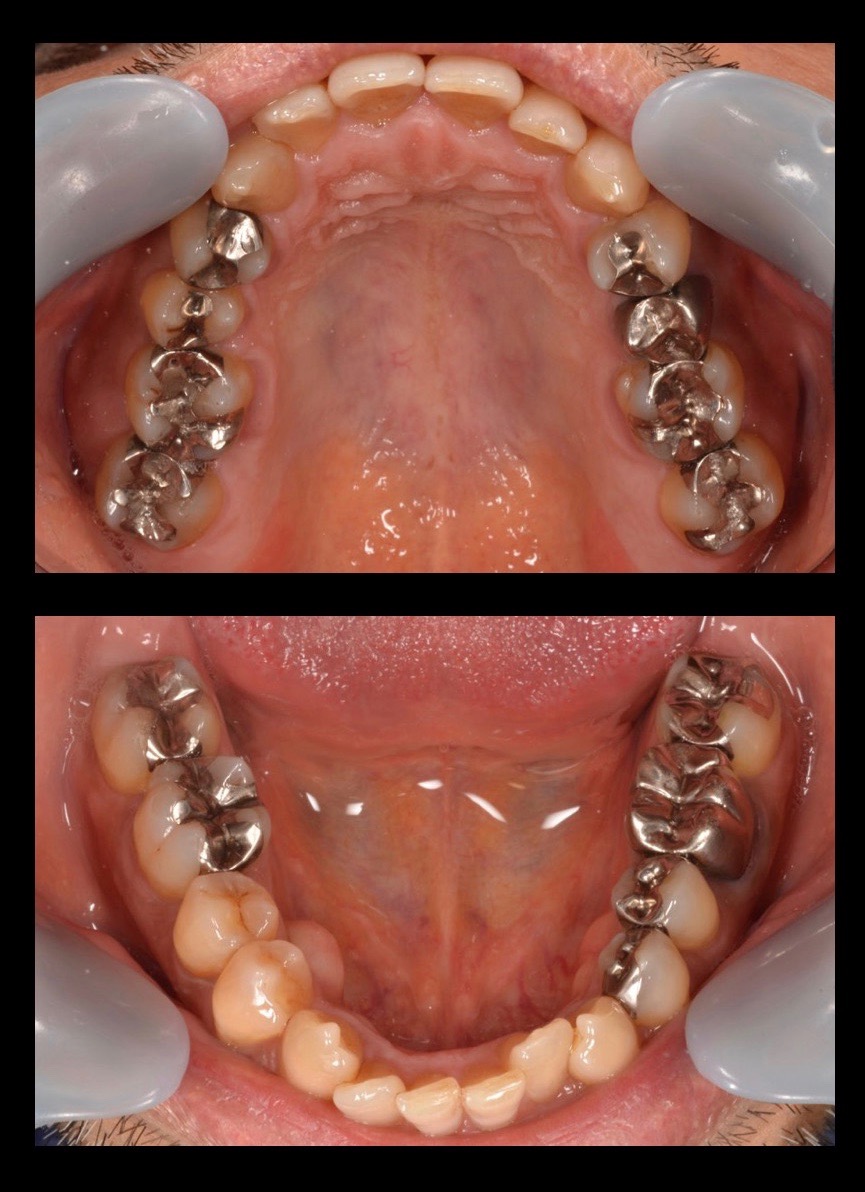

★メタルフリー治療

50代男性の、銀歯をなくしたいというご要望の症例です。レントゲンで発見された銀歯の下の虫歯を治療し、金属アレルギーのリスクもないセラミックで補綴。治療期間は2週間の短期間で、口の中が非常にスッキリした。味覚が良くなり食事が楽しみになったとのこと。

| リスク・副作用 | 治療終了後のメンテナンス不足による歯周病 歯ぎしりや過剰な噛み締めによるセラミックスの破折 |

|---|---|

| 費用 | 10万円/1本(税別) |

| 期間 | 2週間 |